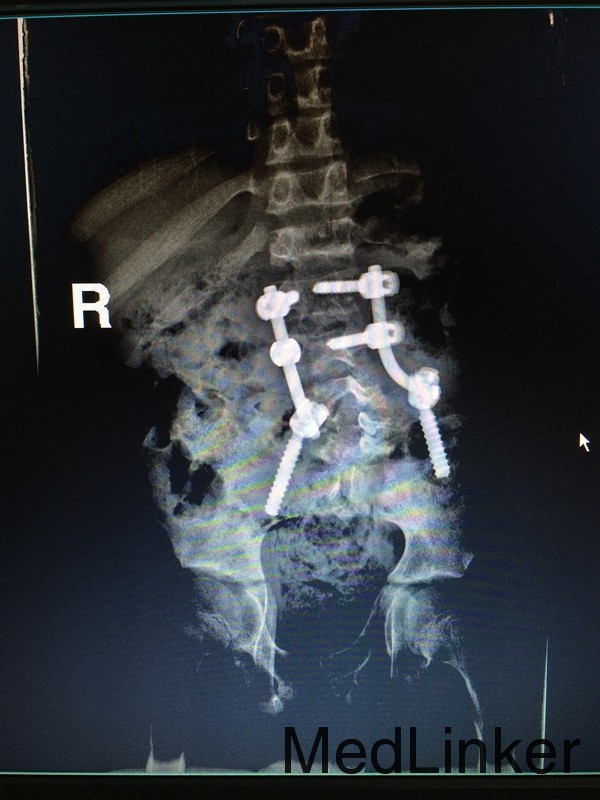

诊断:脊髓栓系综合症 治疗:神经外科联合骨科在全麻下行脊髓栓系松解、椎板修补术,术后予对症支持治疗。

随访:患者双下肢活动感觉较前稍好转。 讨论:脊髓位于脊椎管中,人在生长发育过程中,脊椎管的生长速度大于脊髓,因此脊髓下端相对于椎管下端逐渐升高。脊髓栓系即脊髓下端因各种原因受制于椎管的末端不能正常上升,使其位置低于正常。它是多种先天性发育异常导致神经症状的主要病理机制之一,由此而导致的一系列临床表现即称为脊髓栓系综合征,又称脊髓拴系综合征。